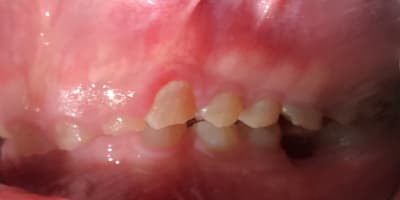

Bonjour je suis lenovo ici . Quelqu’un pourrait-il me donner toutes les étapes pour faire ce cas ? Que faut-il faire précisément ? Le patient n’a pas de contraintes financières. Pas de lésions apicales. Uniquement des usures de dents.

Les photos ne sont pas dingues, mais les usures semblent très majoritairement antérieures. Pourquoi?

Et le fait que 17 18 27 28 semblent intactes alors qu'apparemment il y a des antagonistes intactes aussi